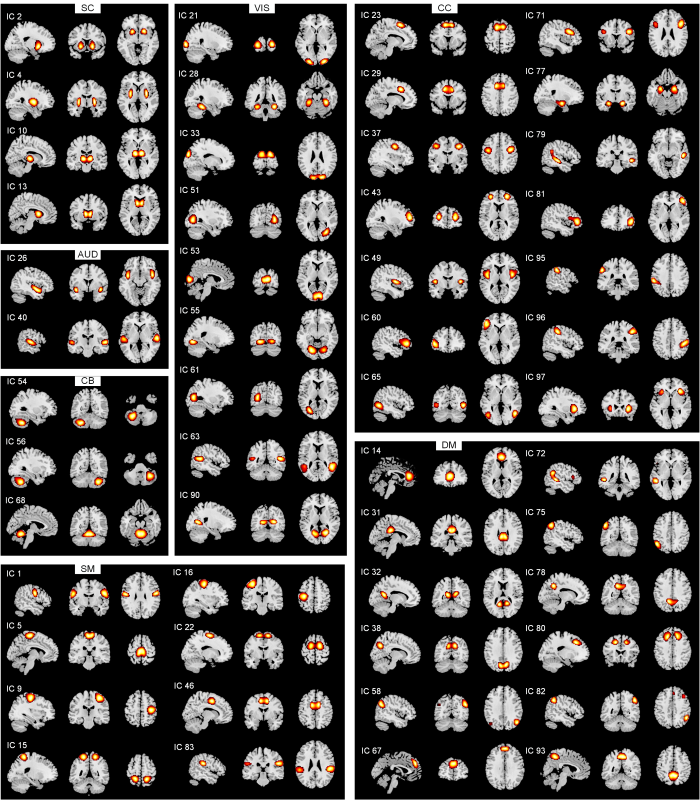

2.2 独立成分网络

所有52个IC的空间图,使用组ICA识别,详细信息及空间图如图1所示.根据其解剖和功能特性,将独立组件分为以下七个网络:皮层下(subcortical,SC)、听觉(auditory,AUD)、感觉运动(sensorimotor,SM)、视觉(visual,VIS)、认知控制(cognitive control,CC)、默认模式(default mode,DM)和小脑(cerebellum,CB).

7网络中的52个IC的空间图(空间图阈值为t > µ + 5σ)

Spatial maps for the 52 independent components grouped into seven functional networks (spatial maps were thresholded with t > µ + 5σ)